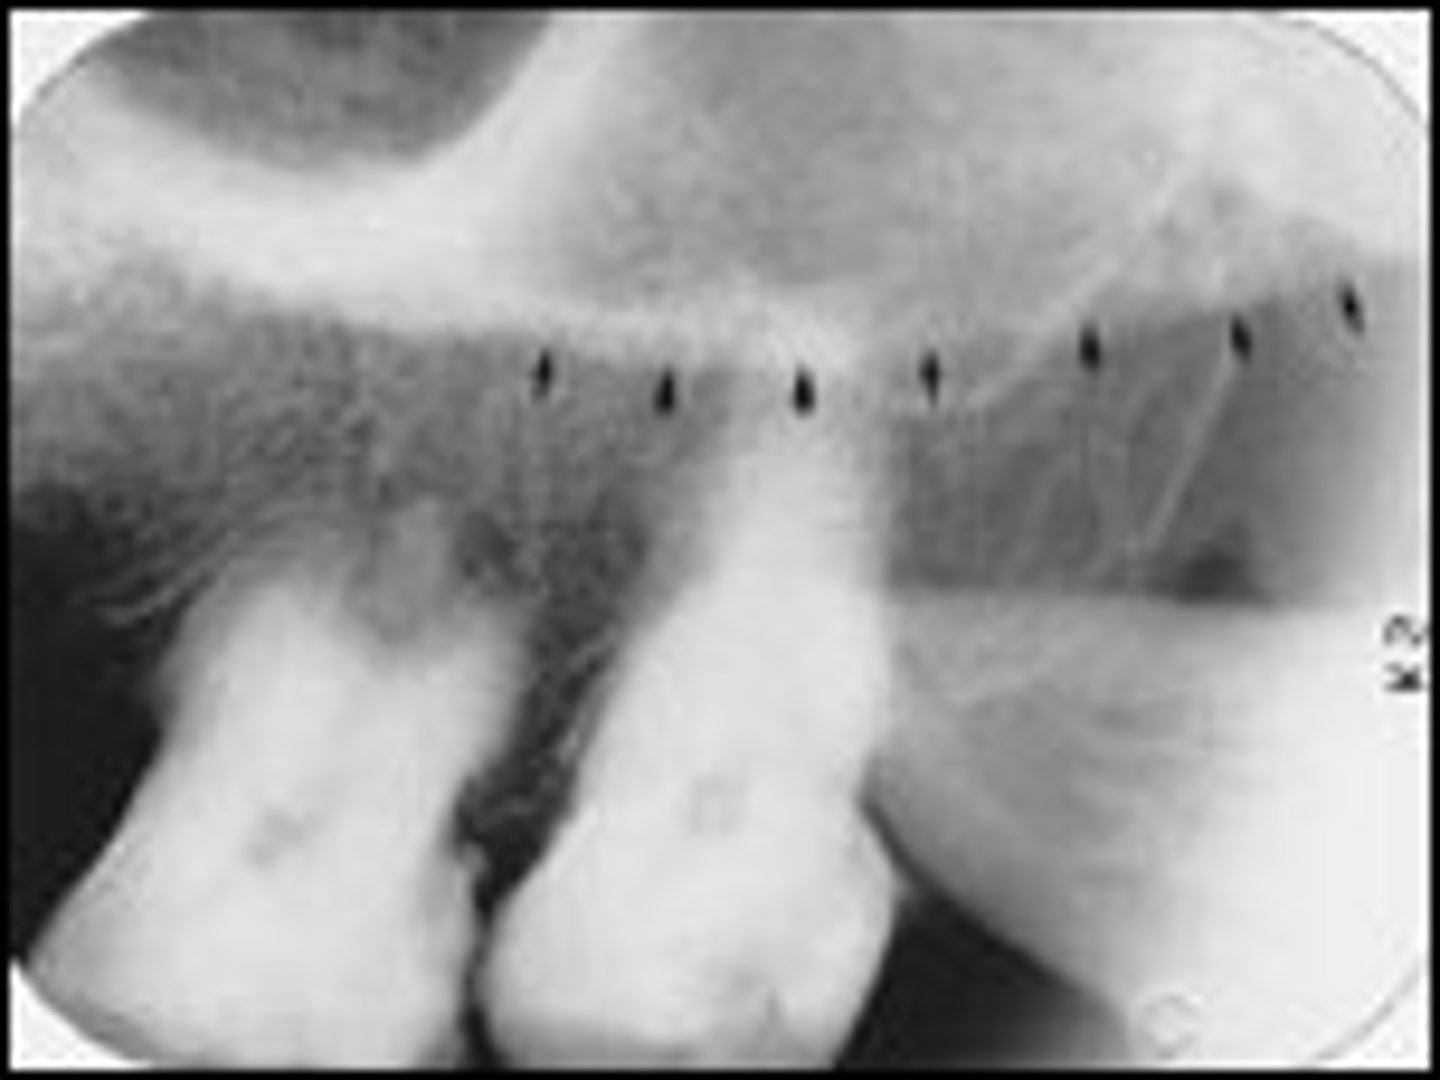

median suture

"crack" between roots of maxillary central incisors

area of incomplete fusion

radiolucent

incisive foramen

hole in the bone of the maxilla and between roots of incisors